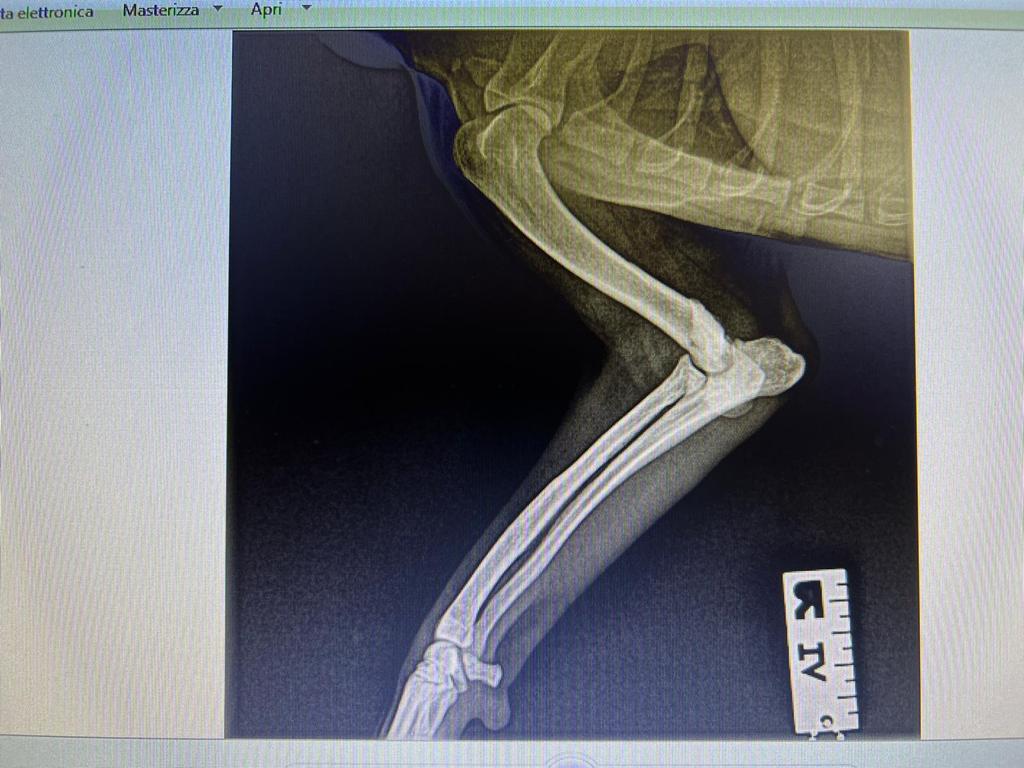

Rüde, Mischling, 3 Jahre, Vermittelt, stammt aus Italien, TierNr. 5213

Bullo wurde trotz seines gesundheitlichen Päckchens, ohne wenn und aber adoptiert. Kennengelernt wurde er auf seiner Pflegestelle immer mal wieder, denn die neue Familie wohnt im gleichen Ort. Bullo liebt Menschen und davon gibt es im neuen Zuhause jede Menge. Wir freuen uns, das der kleine Schatz das Sprungbrett Pflegestelle nutzen konnte für sein ganz großes Glück.